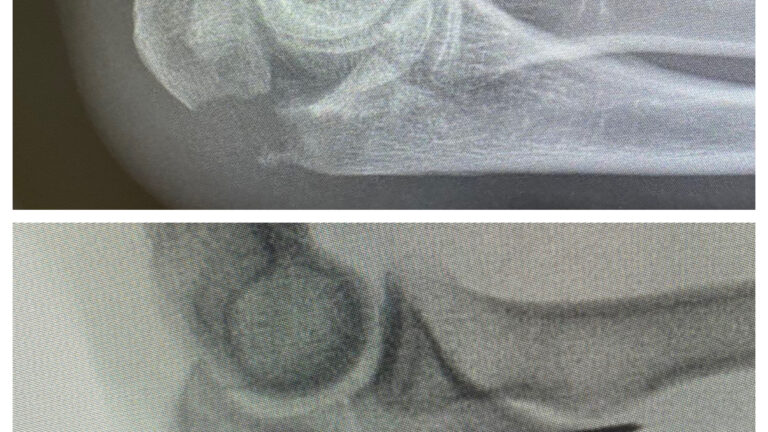

Kyynärpäämurtuma

Murtumakuvia

Ennen – jälkeen